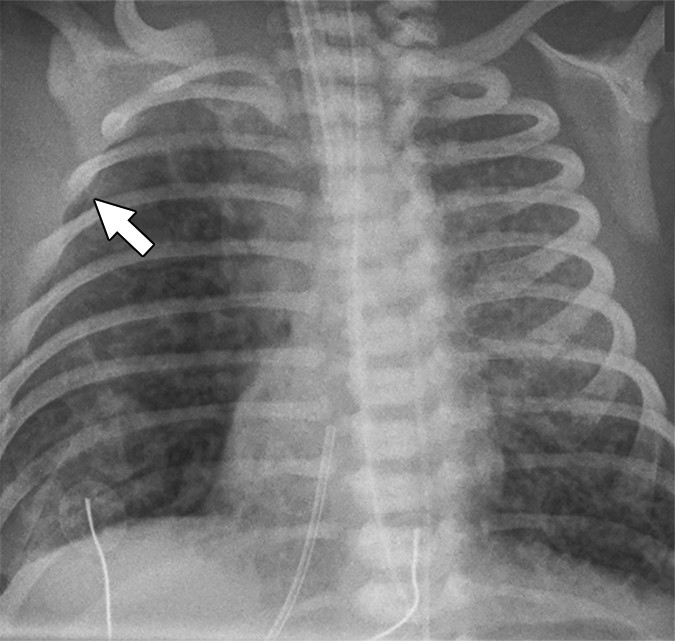

PIE (Pulmonary Interstitial Emphysema) Linear and cystic lucencies radiating from hilum; can be unilateral or bilateral Complication of mechanical ventilation in HMD; air dissects into perivascular and perilymphatic spaces

PIE is a ventilator complication distinct from pneumothorax — the air is interstitial, not pleural. Unilateral PIE may be managed with selective intubation of the contralateral bronchus. Bilateral PIE carries significant morbidity.